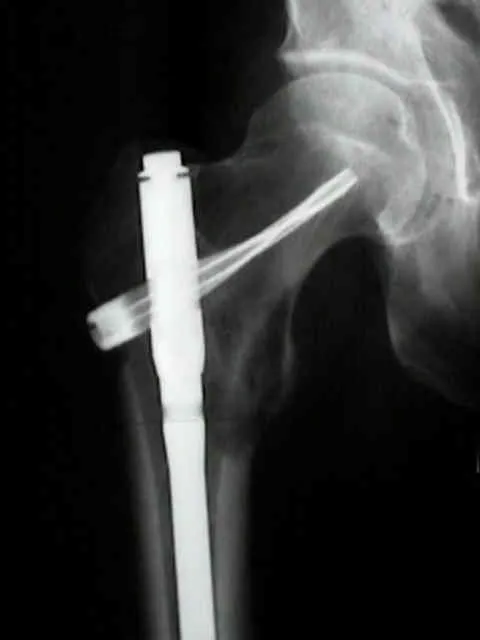

- Mirel's Score: Predicts pathological fracture risk in long bones.

- Factors: Site, Pain, Lesion type (lytic/blastic), Size of lesion.

- Score ≥ 9: Prophylactic fixation recommended.

- Score ≤ 7: Non-operative management.

⭐ A Mirel's score of 8 is considered borderline, requiring individualized decision for fixation.

- Surgery: Pathological/impending # (Mirels score >8), spinal cord compression, instability, solitary lesion.

- Procedures: Internal fixation, arthroplasty, excision.